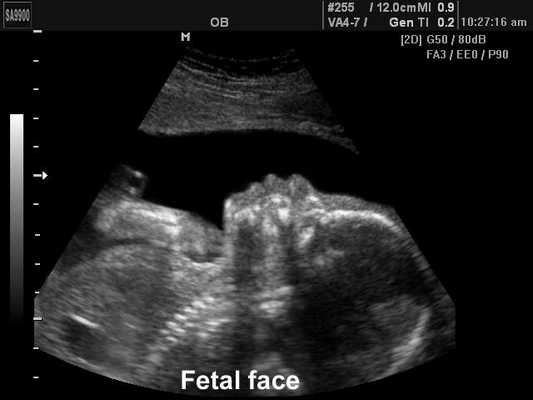

Лицо плода, B-режим

[EN] Эхограмма №192: Лицо плода в B-режиме.

Изображение получено с помощью УЗ сканера SonoAce-9900 (снят с производства).